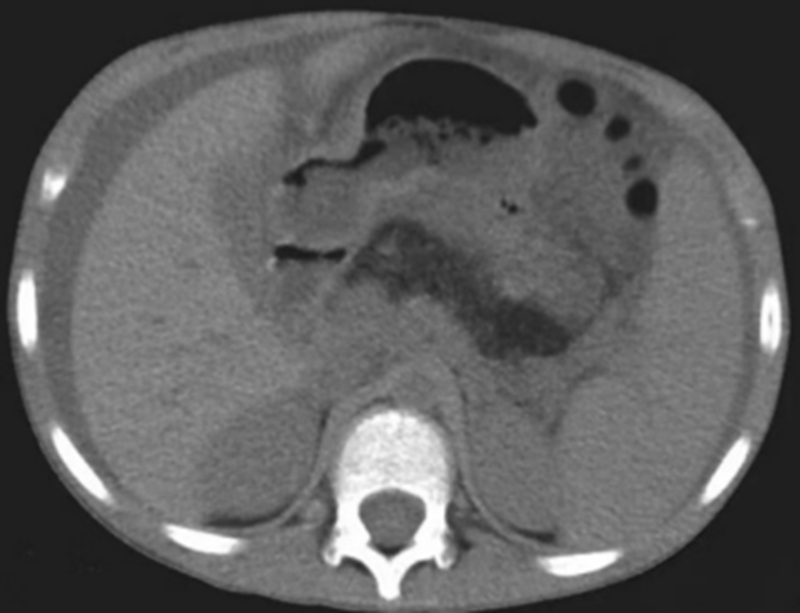

CT 所示胰腺区脂肪密度影

该病十分罕见,患儿常以脂肪泻、肝酶异常为首发症状,随后会出现反复感染、生长缓慢、骨骼异常、血细胞减少等表现,需要通过大便脂肪含量、血清胰酶、胰腺影像学、骨髓细胞学分析及基因检测才能最终确诊。